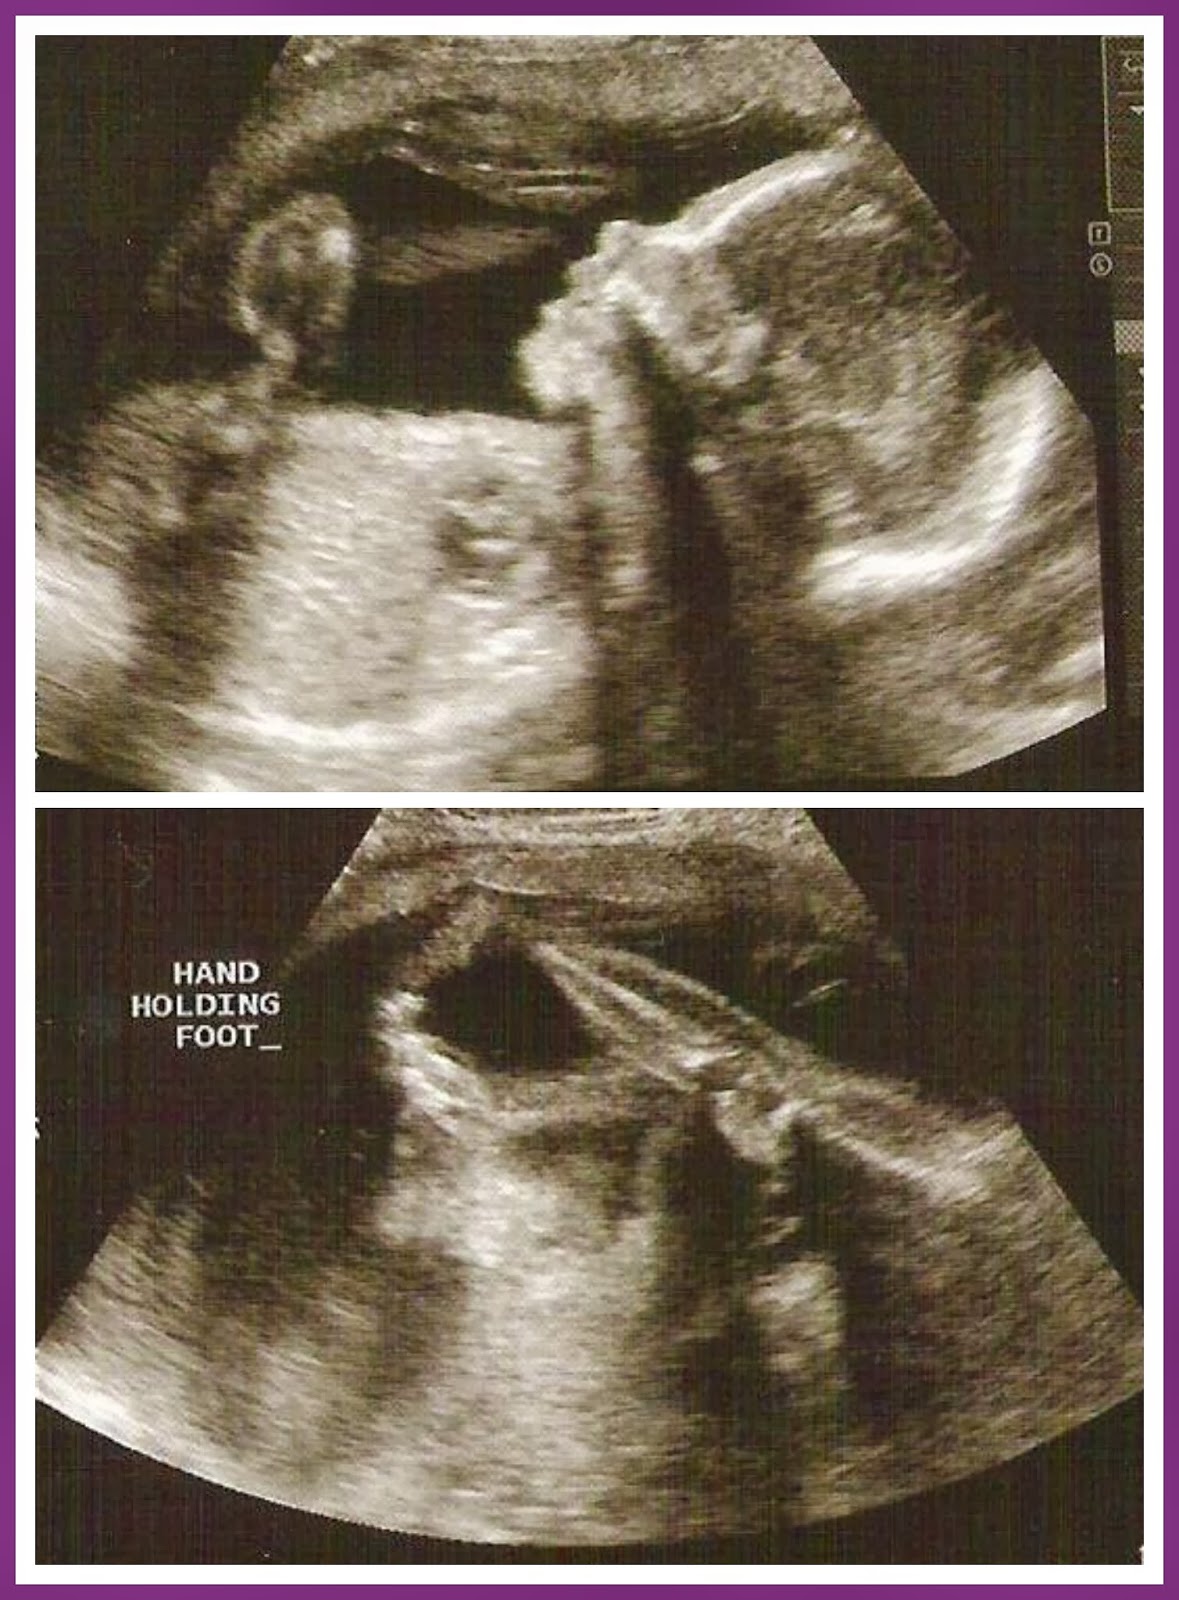

When we went ot our doctor's appointment on Tuesday, baby girl was doing all kinds of gymnastics moves!  She had her foot in her hand and raised it above her head at one point!  It feels so great to see her moving and hear her heart beating!  Landon always requests for the Sonographer to let him hear her heart beat.  He's very interested in whether she's kicking or not and loves to place his hands on my belly.